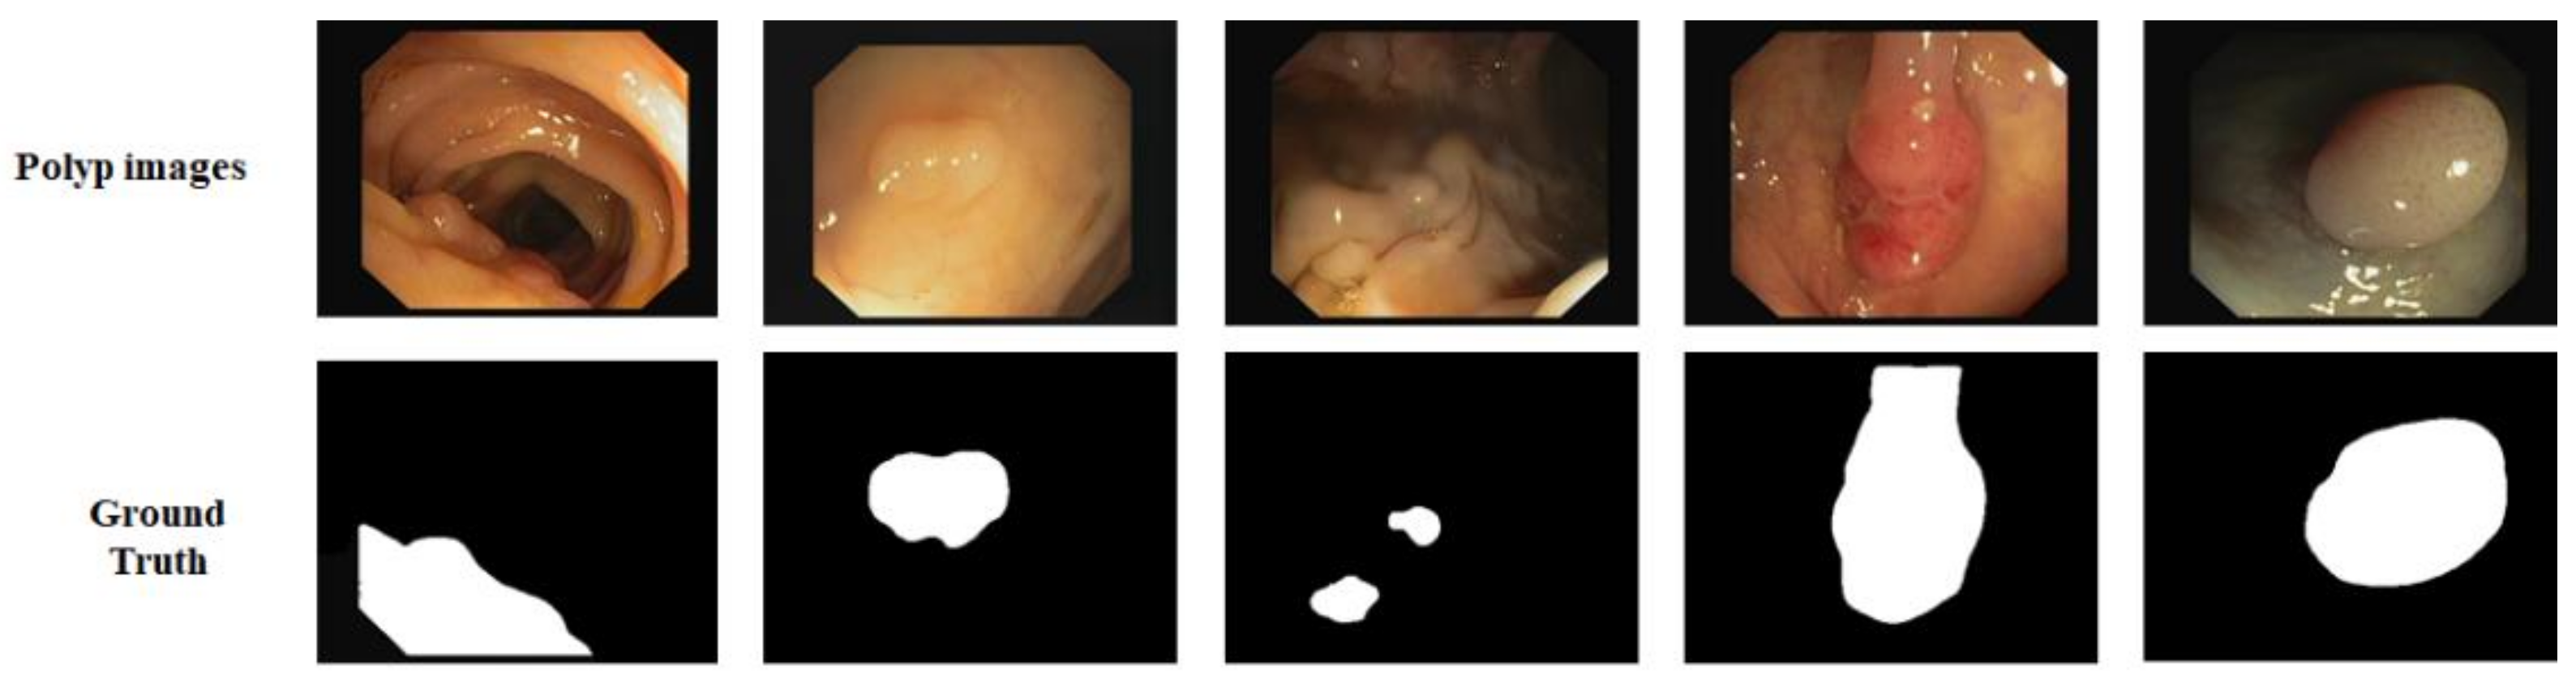

CVC-612: In addition, we used the CVC-612 [49] dataset, this database built in collaboration with the Hospital Clinic of Barcelona, Spain. CVC-612 has been generated from 23 different video studies from standard colonoscopy interventions with white light. CVC-612 database comprises 612 polyp images of size 576 × 768 pixels from 31 colonoscopy series. The images were split into training, validation, and testing sets in the ratio of 80:10:10. All training, validation, and testing were performed with an image size of 224 × 224 pixels. Figure 6 shows some example images and corresponding masks from the CVC-612 dataset.

Figure 6. Images and ground truth masks from the CVC-612 dataset.